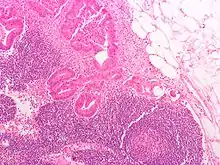

Definitive staging can only be done after surgery and histopathology of colorectal carcinoma. An exception to this principle would be after a colonoscopic polypectomy of a malignant pedunculated polyp with minimal invasion. Preoperative staging of rectal cancers may be done with endoscopic ultrasound. Adjunct staging of metastasis include abdominal ultrasound, MRI, CT, PET scanning, and other imaging studies.

Dukes classification

In 1932 the British pathologist Cuthbert Dukes (1890–1977) devised a classification system for colorectal cancer.[3] Several different forms of the Dukes classification were developed.[4][5] However, this system has largely been replaced by the more detailed TNM staging system and is no longer recommended for use in clinical practice.[6]